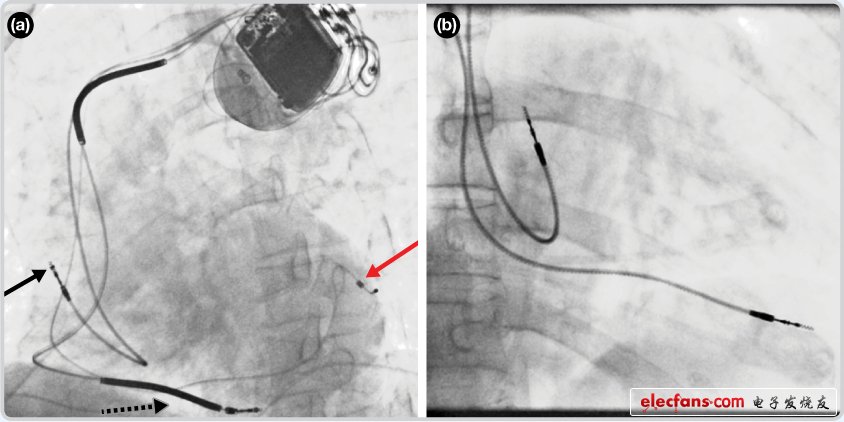

4235 德國海德堡大學醫(yī)院心臟科醫(yī)生本杰明?梅德用鼠標和電腦屏幕代替了手術刀和手術室,小心翼翼地將起搏器的電極放入跳動的3D打印心臟中。在手術開刀之前,為了檢驗起搏器是否能讓充血性心力衰竭患者繼續(xù)存活,梅德對7497位患者心臟細胞的電特性和物理特性進行了模擬。

1354 研究人員表示,這是首次實現利用消融導管結合近紅外光譜學映射,成功區(qū)分心捐贈與心血管疾病患者各種組織的類型。目前,大多數臨床心臟測繪系統(tǒng)都是基于功能測量,如能將提供底層組織組成信息的光學測量與標準功能方法共同使用,可以顯著提高消融成功率。